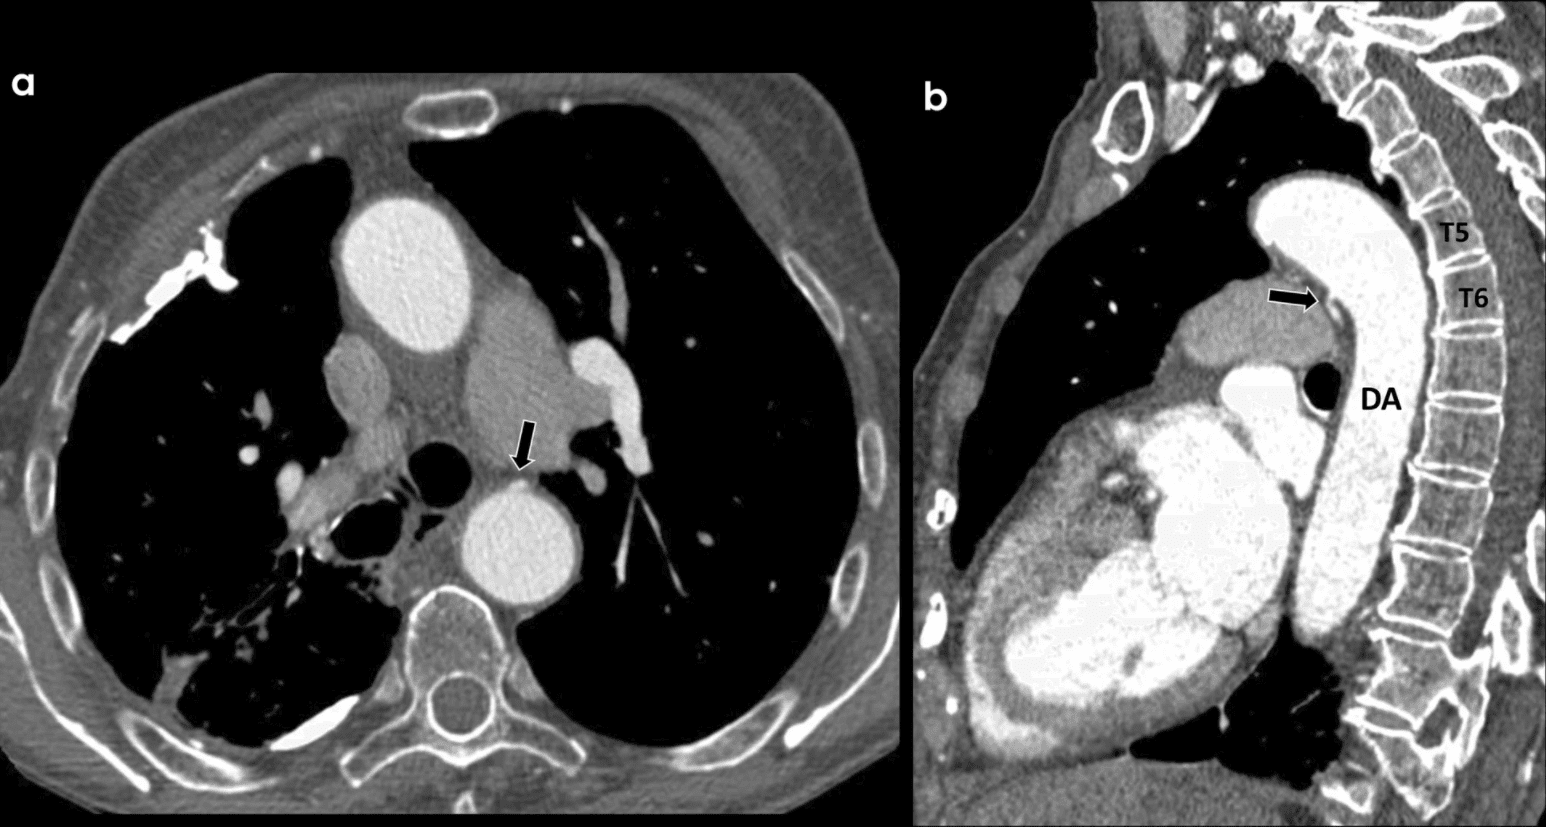

– Trong y văn, cụm từ động mạch phế quản dùng để chỉ các động mạch phế quản chính thức xuất phát từ động mạch chủ xuống, ngang D5-D6 (95%) – gần ngang mức carina và các động mạch phế quản lạc chỗ (2-4%) xuất phát từ phần cao ngang D4 hoặc phần thấp ngang D8 của động mạch chủ ngực hoặc xuất phát từ động mạch dưới đòn, động mạch vành, thân động mạch giáp-cổ. – Khi bắt nguồn từ động mạch chủ xuống, các động mạch phế quản phải thường phát sinh từ thành sau-bên, trong khi các động mạch phế quản trái bắt nguồn từ thành trước hoặc bên, cả hai đều chạy ra sau khí quản và phế quản chính về phía rốn phổi. – Type 1 (3 nhánh): 1 thân chung động mạch phế quản – liên sườn phải + 2 động mạch phế quản trái. – Động mạch phế quản nhỏ và mảnh, sau khi qua rốn phổi chia nhỏ dần để vừa cho nhánh chạy tùy hành cùng các ống phế quản cho tới ngang phế quản tận cùng thì tỏa thành búi mao mạch hòa cùng lưới mao mạch phổi quanh phế nang vừa cho nhánh động mạch xiên vào thành quản tạo thành lưới mao mạch thứ 2 trong thành phế quản. Hai mạng lưới mao mạch trên hòa nhập với nhau ở ngoại vi của phổi rồi dẫn lưu theo tĩnh mạch phế quản hoặc tĩnh mạch phổi về tuần hoàn chung. – Một nhóm mạch thứ 3 có liên quan tới tuần hoàn phế quản phổi có tên gọi là các động mạch thuộc phế quản. Đó là các động mạch nằm trong lớp cơ thành ngực và chia nhánh nuôi là thành màng phổi: nhánh từ động mạch dưới đòn, động mạch liên sườn, động mạch vú…nhưng khi phần phổi sát thành ngực hoặc màng phổi bị tổn thương mạn tính thì chúng xuyên vào phổi, nối với hệ mạch phế quản – phổi và tình trạng ứ máu có thể tăng lên. * Nguyên nhân tuần hoàn * Nguyên nhân hô hấp * Dị sản động mạch phế quản – Động mạch phế quản tách từ động mạch chủ xuống ngang mức D3 tới D8, trong đó 80% ngang mức D5-D6. – Hình ảnh giả phình động mạch phế quản. – Tổn thương phối hợp: giãn phế quản, hình kính mờ hoặc tổn thương dạng khảm (khi có ho máu), tổn thương lao cũ, phình động mạch phế quản, huyết khối động mạch phổi… => Case lâm sàng 1: => Case lâm sàng 2: => Case lâm sàng 3: => Case lâm sàng 4: => Case lâm sàng 5: => Case lâm sàng 6: => Case lâm sàng 7: => Case lâm sàng 8: => Case lâm sàng 9: => Case lâm sàng 10: – Là phương pháp hiện được áp dụng phổ biện tại nhiều cơ sở y tế trong điều trị can thiệp nút mạch những trường hợp giãn ĐM phế quản có biến chứng ho máu.II. Giải phẫu

– Đường kính động mạch > 2mm.

– Động mạch phế quản giãn ngoằn ngoèo.2. Chẩn đoán DSA